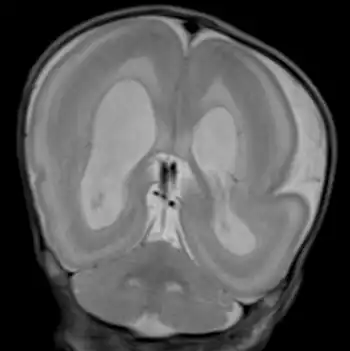

With the use of prenatal ultrasonographic imaging, early detection of abnormal brain development in the fetus with MDS can be seen. At birth, facial dysmorphism can be present in the infant. Young children, when affected, can have feeding difficulties, severe intellectual disability, developmental delay, and seizures. MRI facilitates early detection of this syndrome in children by revealing a "smooth brain" image, also called lissencephaly.[7] Children with this syndrome may remain underdiagnosed because of rarity and the prevalence of facial features that appear to be dysmorphic. The syndrome shares distinct external features (phenotype) similar to more common syndromes. Lack of relevant family history may delay diagnosis. FDNA provides a service that in turn increases the chances of detecting these distinct characteristics, which, when shown to a geneticist, can assist in reaching the right medical diagnosis. If a couple has had one child with MDS, they can be offered prenatal screening in future pregnancies. This option is particularly important for the 20% of MDS families where one parent carries a balanced chromosome rearrangement. The risk of these couples having another child with MDS depends on the exact type of chromosomal rearrangement present and may be as high as 25–33%. For families in which both parents' chromosomes are normal, the risk of having another child with MDS is low (1% or less). Either chorionic villus sampling (CVS) or amniocentesis can be used early in a pregnancy to obtain a small sample of cells from the developing embryo for chromosome studies. Early prenatal diagnosis by ultrasound is not reliable because the brain is normally smooth until later in pregnancy. Couples who are considering prenatal diagnosis should discuss the risks and benefits of this type of testing with a geneticist or genetic counselor.

Visuals of the brain

The brain is usually grossly abnormal in outline when someone is diagnosed with Miller–Dieker syndrome. Only a few shallow sulci and shallow Sylvian fissures are seen; this takes on an hourglass or figure-8 appearance on the axial imaging. The thickness and measurement for a person without MDS is 3–4 mm. With MDS, a person's cortex is measured at 12–20 mm.